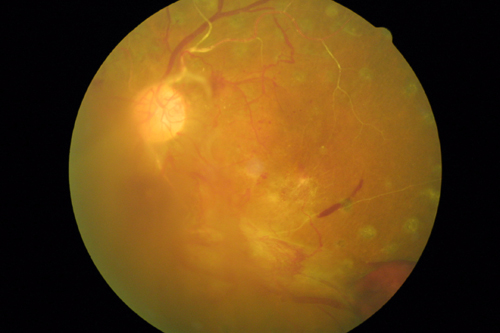

2. 增生性糖尿病視網(wǎng)膜病變(簡稱PDR)

當有新生血管開始沿視網(wǎng)膜表面或視盤開始生長時,即稱之為增生性糖尿病視網(wǎng)膜病變。PDR的主要原因是視網(wǎng)膜的廣泛性血管阻塞阻止了血液的正常流通,血管即因局部缺氧而增生用以供應(yīng)缺血的視網(wǎng)膜。但是,新生的血管會帶來壞處,它不僅容易破裂出血且會伴隨纖維組織增生,而纖維組織會并發(fā)嚴重的視網(wǎng)膜脫離。

PDR比NPDR造成更嚴重的視力喪失,其機制如下:

①???????? 玻璃體出血:血管破裂出血流入玻璃體而成。出血會阻擋光線到達視網(wǎng)膜而妨礙視力。血塊通常要數(shù)天、數(shù)月甚至數(shù)年才能完全吸收,當血塊無法吸收完全時,可考慮行玻璃體切割手術(shù)。

②???????? 牽引性視網(wǎng)膜脫離:當出現(xiàn)PDR時,所生成的新生血管及纖維組織收縮會牽拉到視網(wǎng)膜,當牽拉到黃斑部時會發(fā)生視物變形,若發(fā)生視網(wǎng)膜脫離則會導致嚴重的視力喪失。玻璃體切除可使視網(wǎng)膜受到牽扯的情形得到改善,但是應(yīng)及早手術(shù)。手術(shù)愈晚,術(shù)后視力恢復愈差。

③???????? 新生血管性青光眼:若大部分的視網(wǎng)膜血管阻塞時,虹膜就會有新生血管生成。一旦虹膜出現(xiàn)新生血管,房水流出就會受到阻礙,因此眼球壓力就會上升,此時就稱為青光眼。新生血管性青光眼所致后果相當嚴重,因其會損傷到視神經(jīng)。